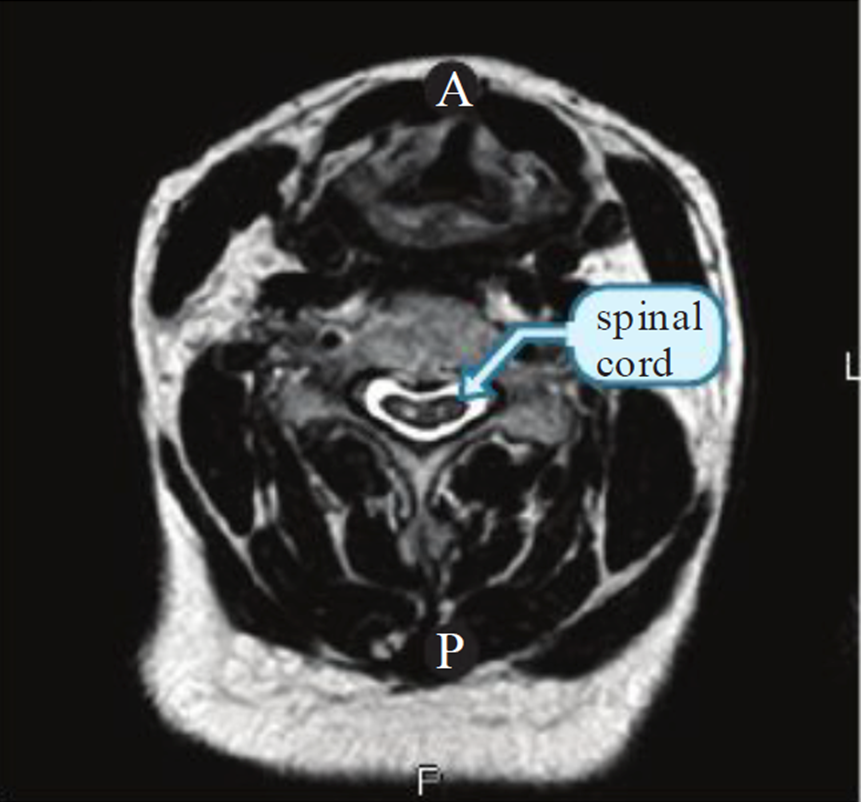

-Mắt rắng (còn gọi là mắt cú) bên trong tủy sống ở mặt phẳng axial trên T2 (hình 2) có thể là hình ảnh nang hoại tử của tủy sống và có tiên lượng xấu (class III).

Hình 2. Mắt rắng (hai điểm tăng tín hiệu) bên trong tủy sống bị chèn ép và teo nhỏ trên phim axial chuỗi xung T2